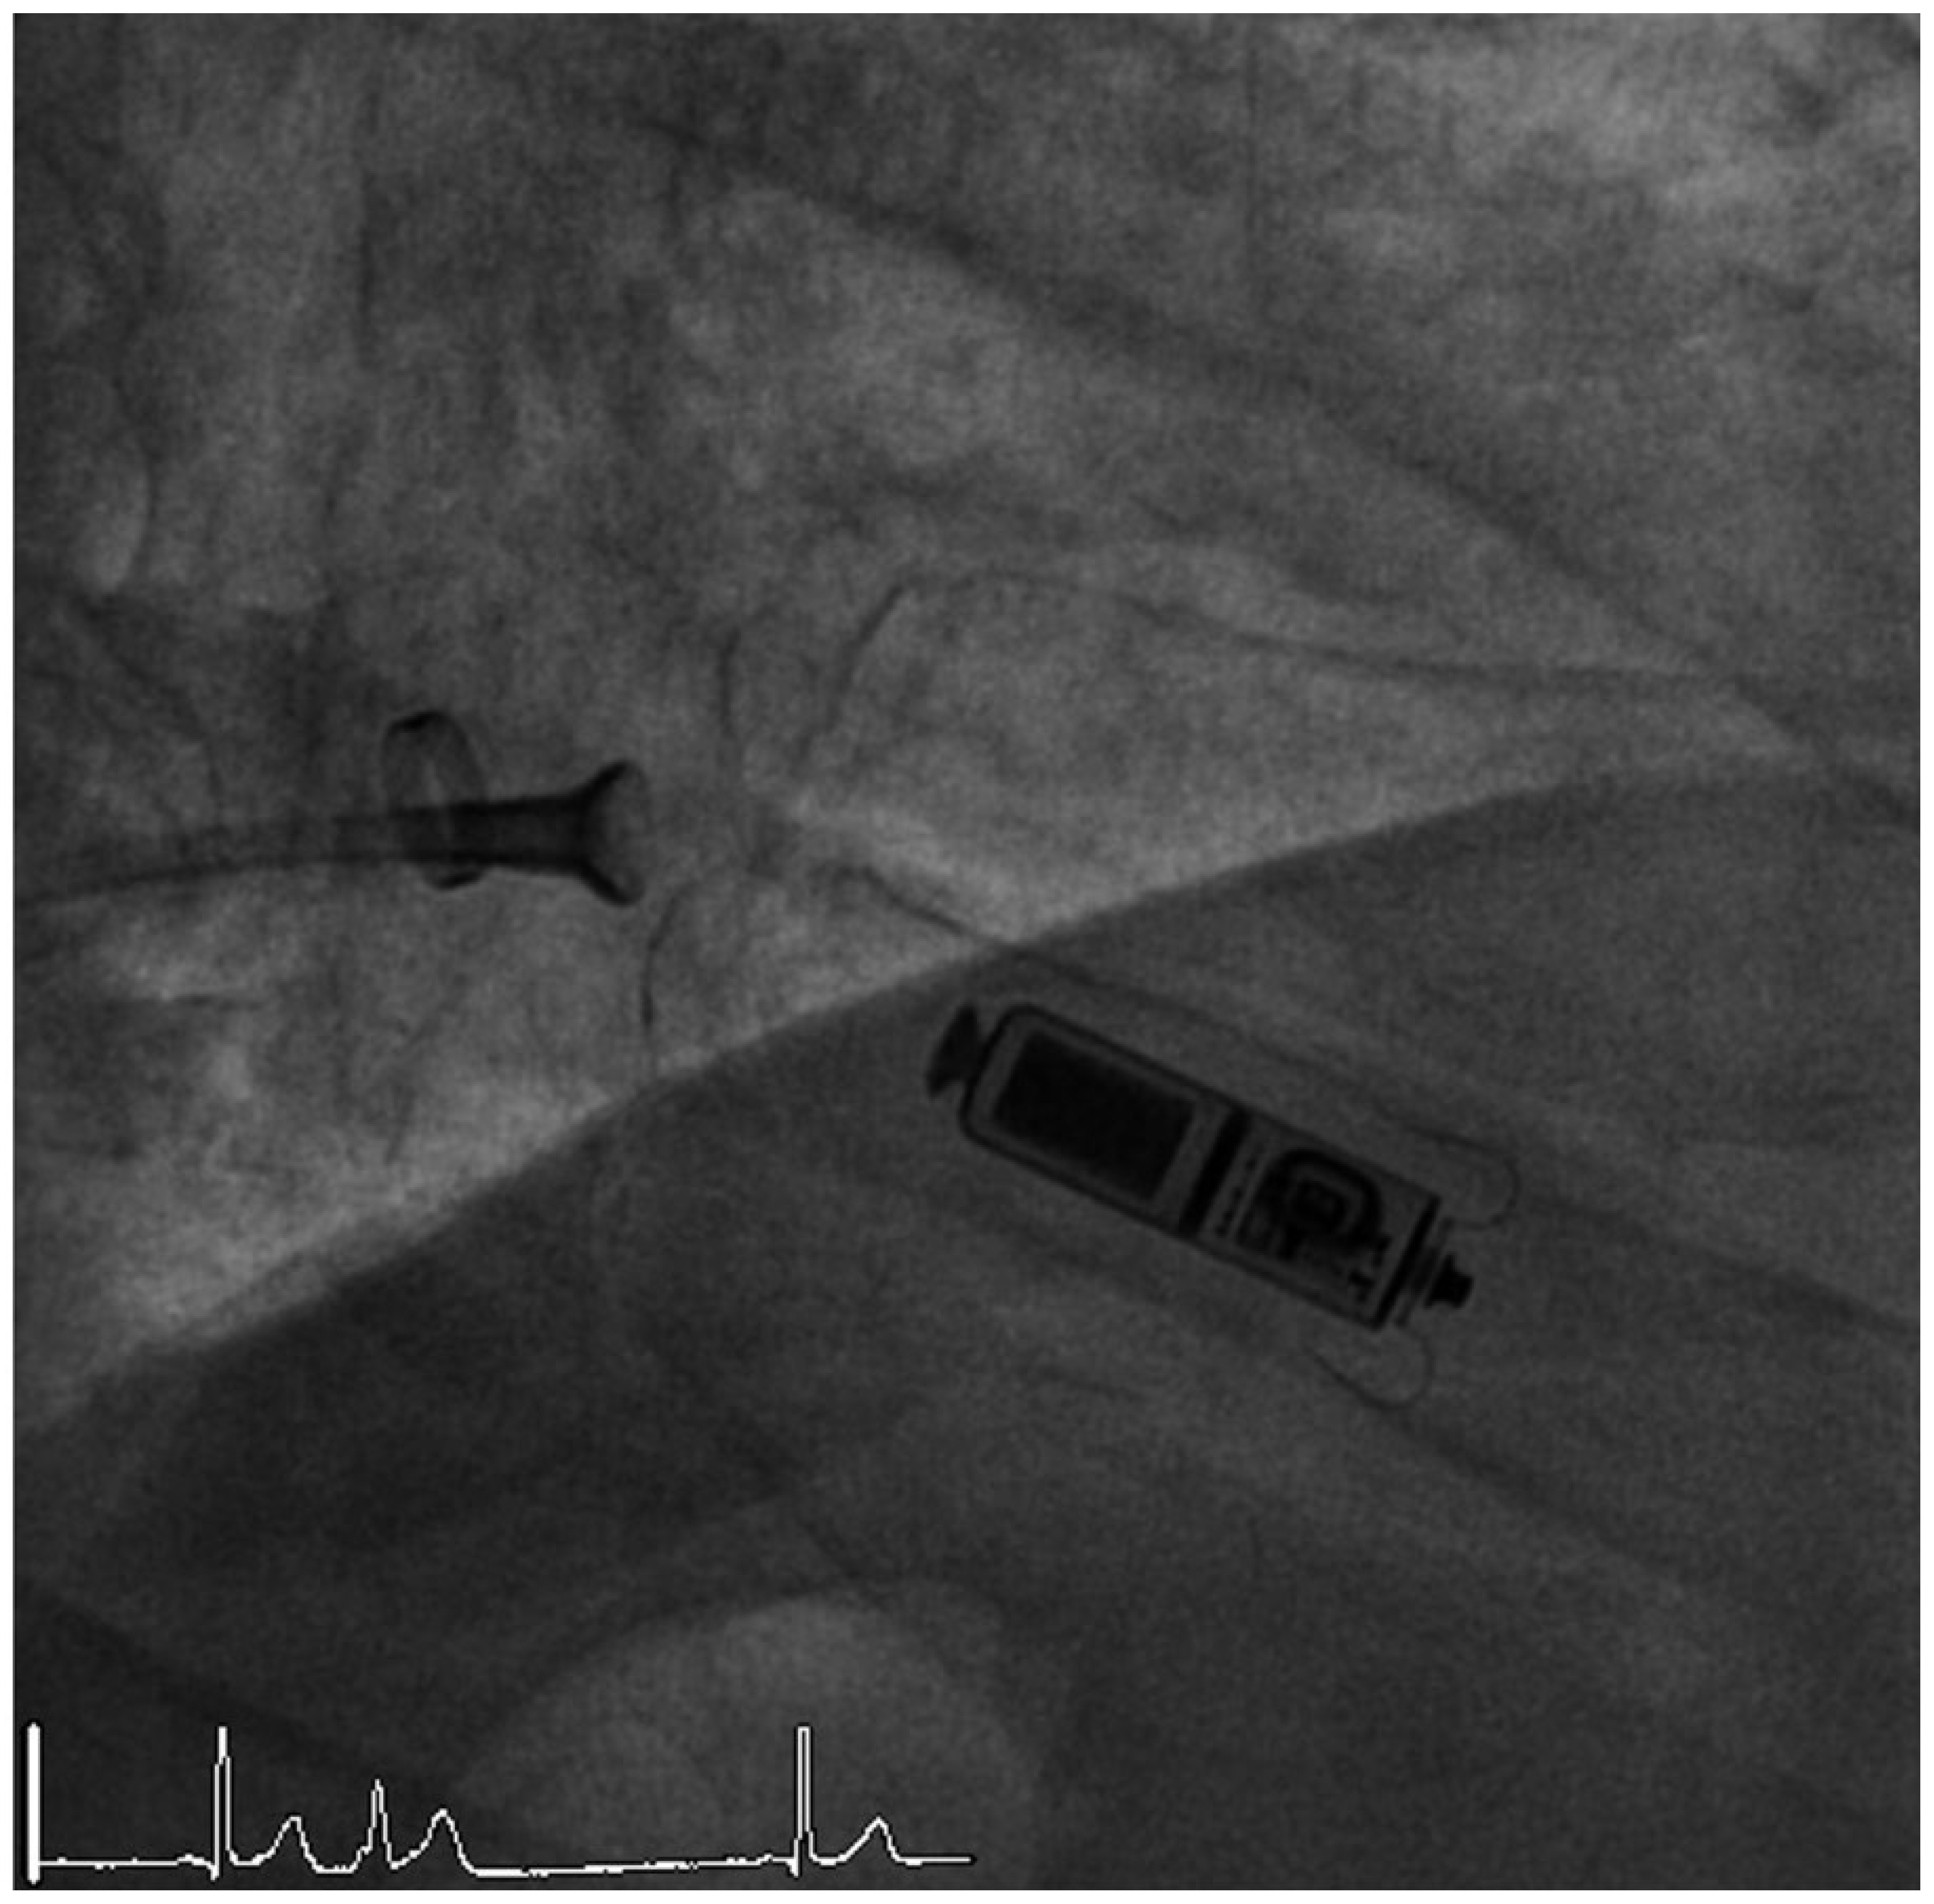

Leadless pacemakers